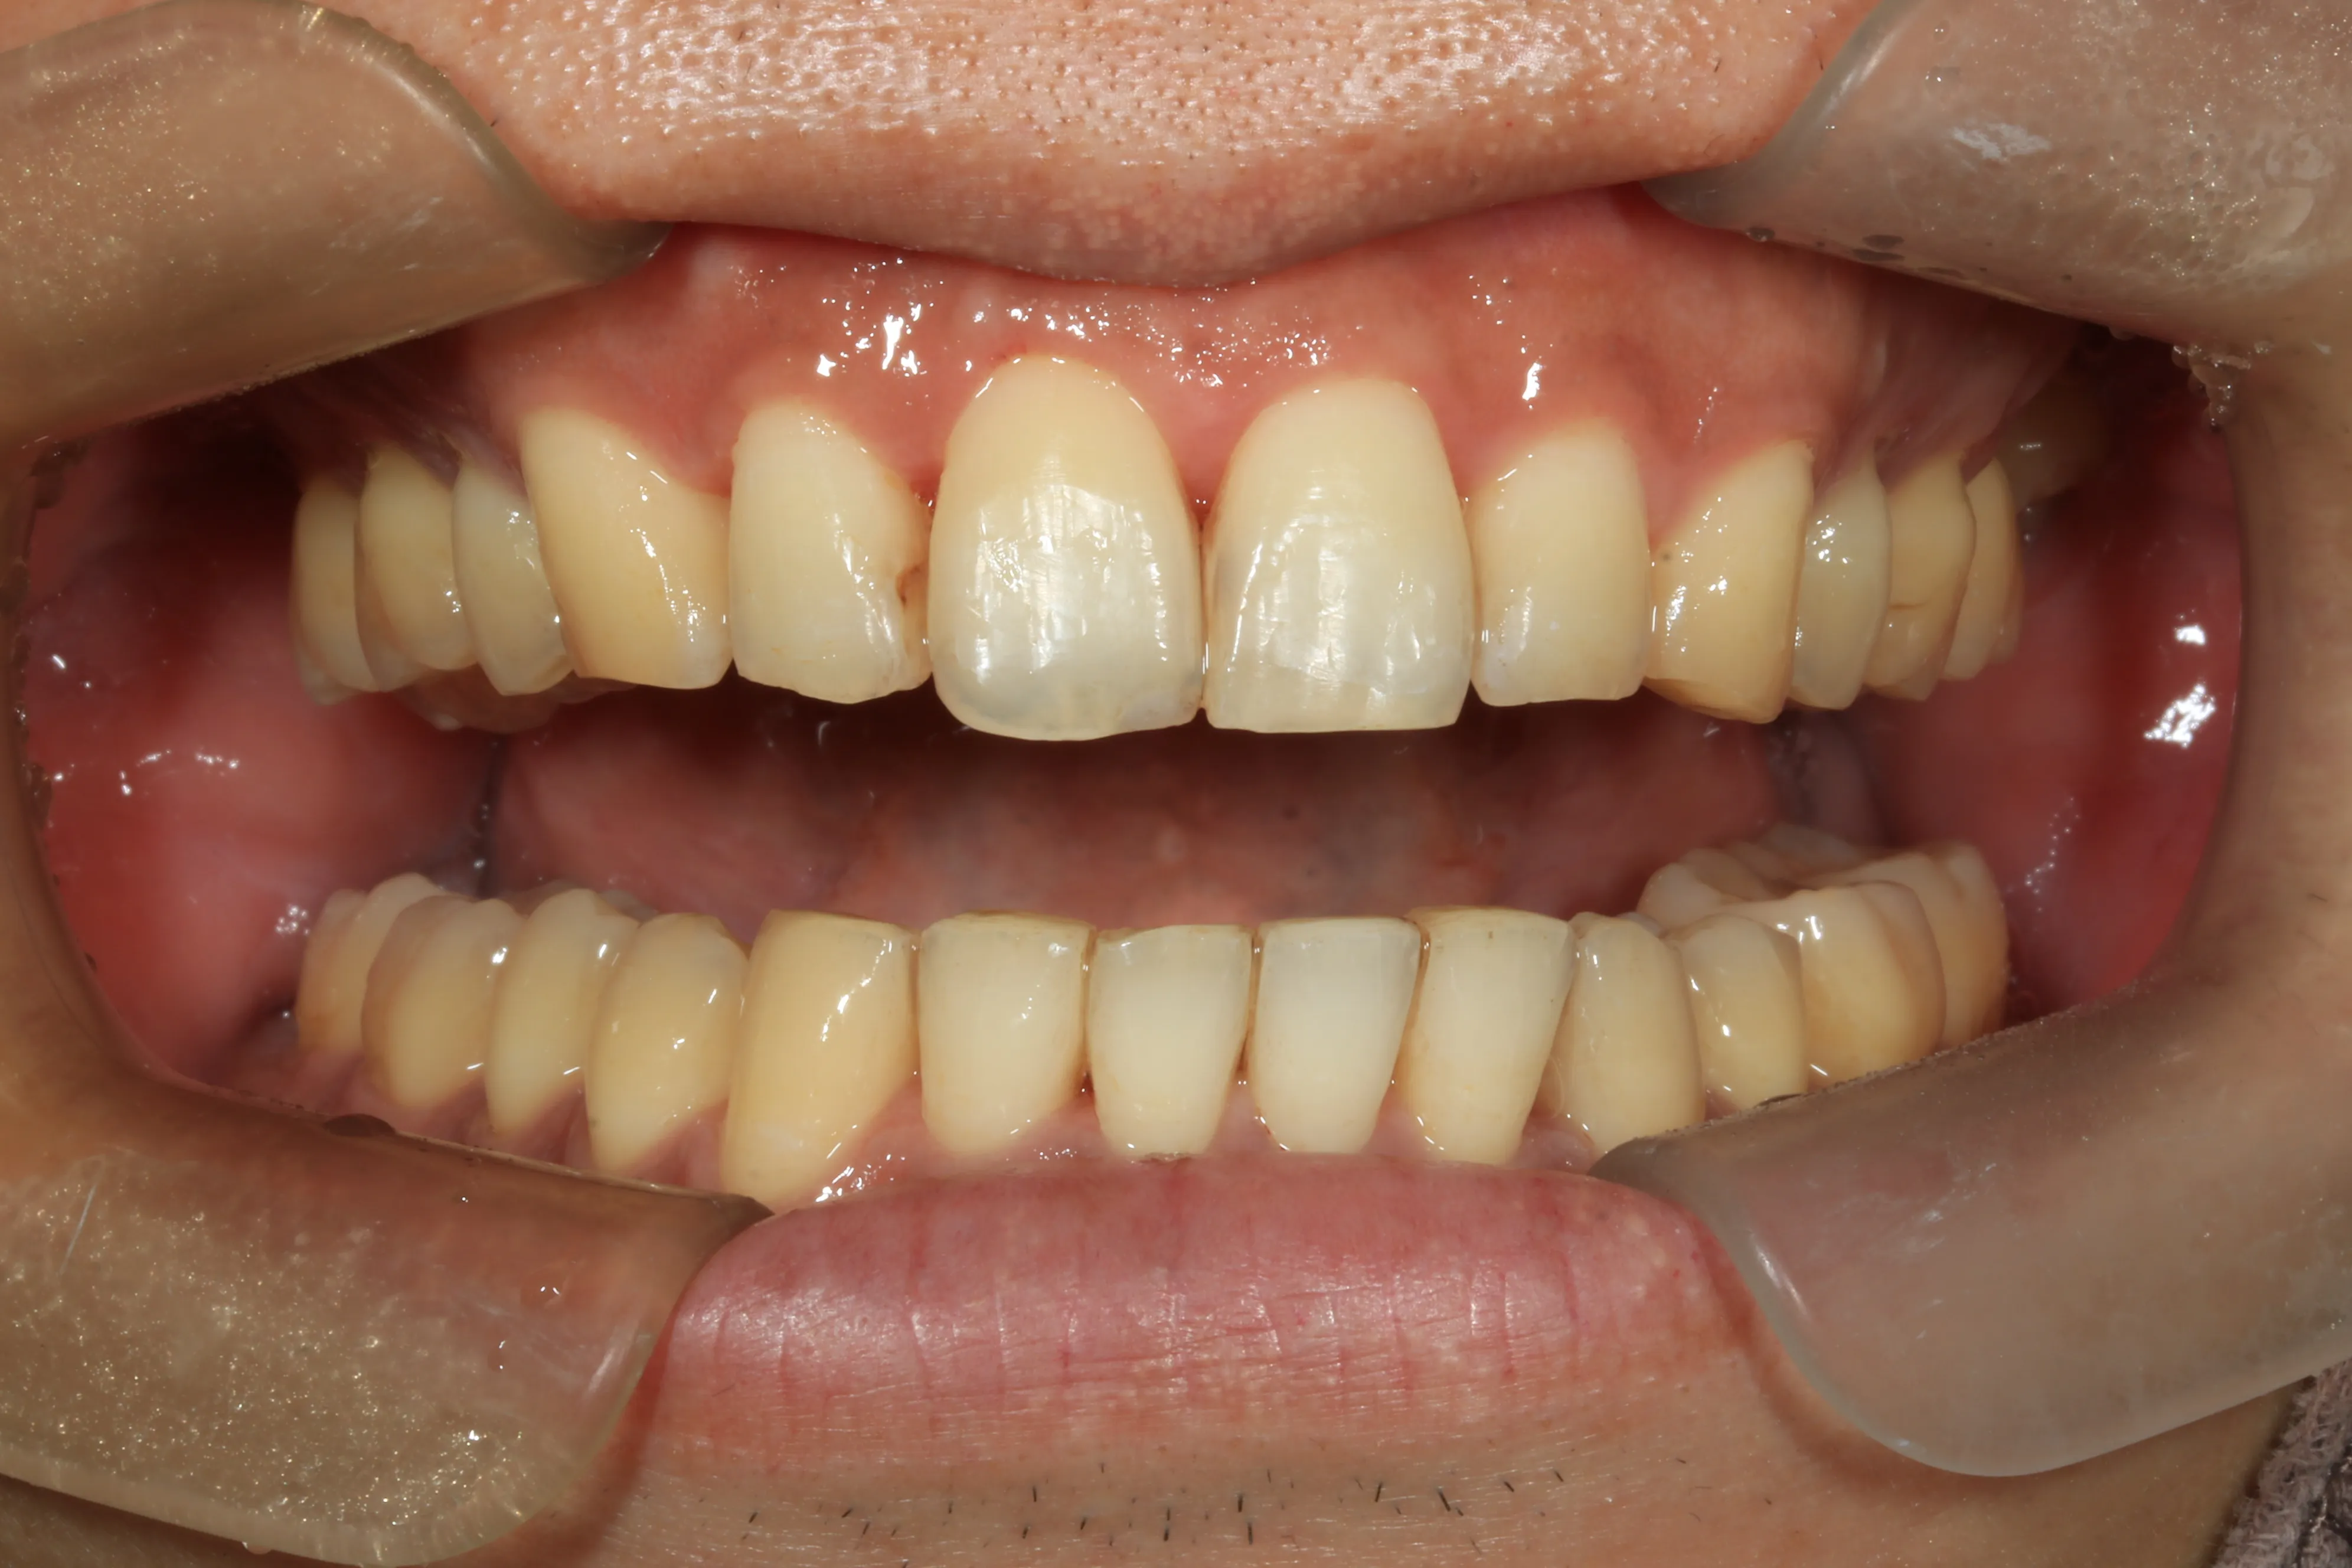

症例④

症例4_治療前 症例4_治療後

年齢・性別 24才男性

治療方法 ホワイトブラケット

治療期間 3年

治療総額 850,000円

特記事項 抜歯あり

リスク・副作用 治療の初期段階では痛みや不快感が生じやすくなりますが、1週間前後で慣れます